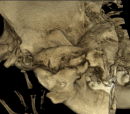

CHANCE (Locked Jaw)

Oh My, is that a tongue that I see hanging out of Chance's Mouth?  Why yes it is.   Our sweet boy can open his mouth a little over an inch and a half comfortably.  He is still adapting to a bit of discomfort in the jaw area but is doing great.  He can eat soft food without any issues and is playing with kibble at this point.

Sweet does not begin to describe this fantastic dog. Chance is gentle and kind to every animal and person he meets.  All he wants to do is give kisses which is something he was not able to do before.   He can also cool himself by panting which was a significant problem he was having before the surgery.  Dogs pant to cool their core body temperature. Your body will over-heat without this ability during hot summer months.  Chance was found as a stray during the hottest days of summer.

It is a Miracle he was able to survive with all the complications that relate to not being able to open your mouth.  Chance is a survivor in a million different ways. We are the lucky ones that are the recipients of his unconditional LOVE.  He is one happy boy that is loving Life because of your generosity. Thanks for caring and making his Journey to Heal and find Love, possible.